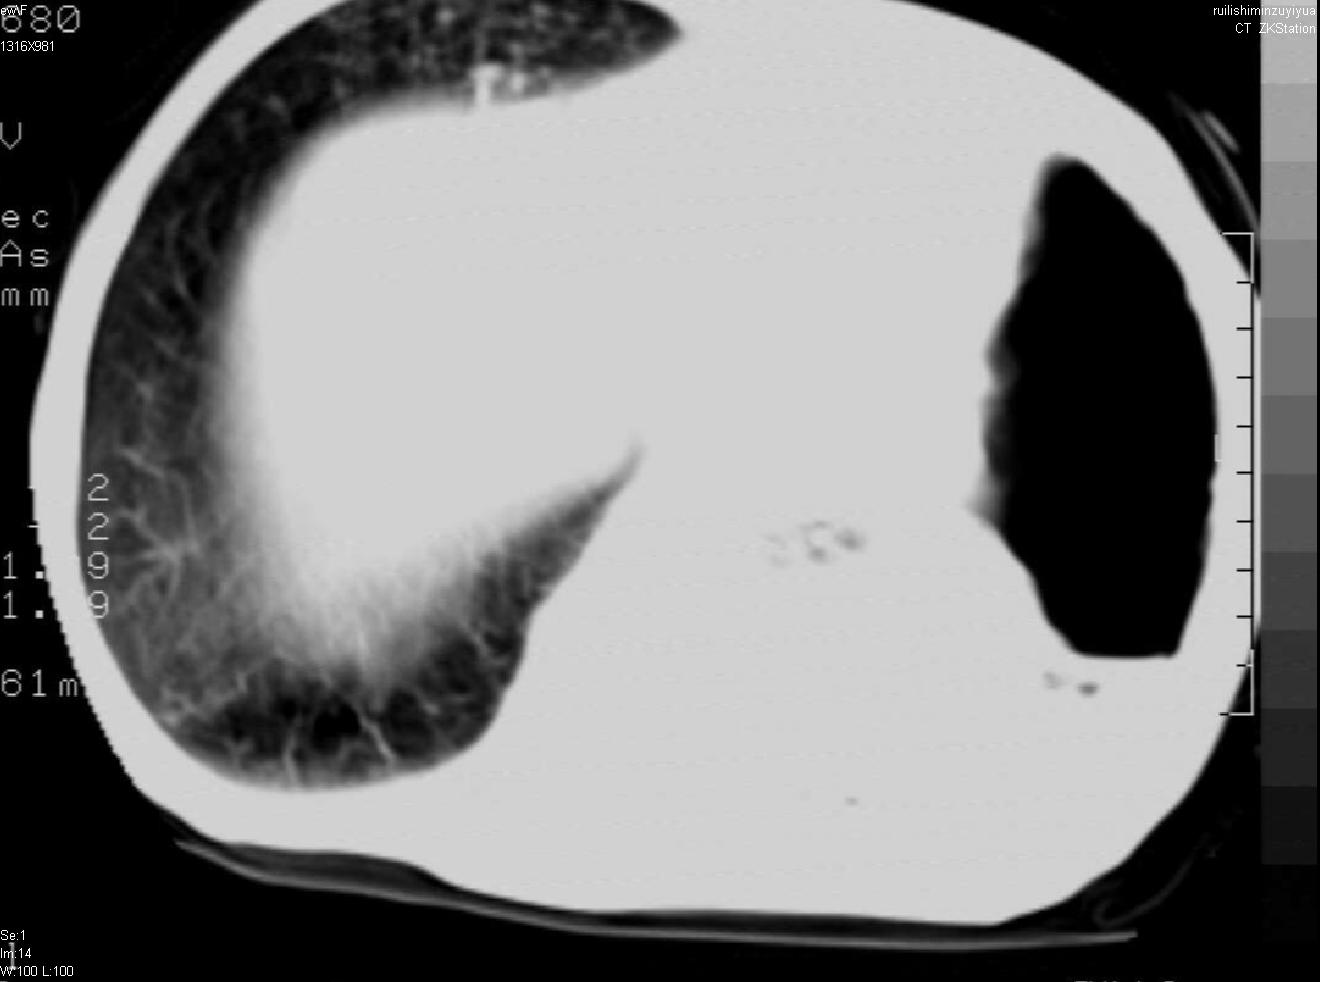

以下是引用avril在2007-6-12 1:17:00的发言:[br]1、左肺毁损。[br]2、左肺多发肺大泡伴自发性气液胸形成。[br]3、右肺继发型结核。

以下是引用天南地北在2007-6-11 23:32:00的发言:[br]1:左侧肺毁损(结核性)伴感染(多发空洞伴液平面)。[br]2:右肺继发型肺结核。